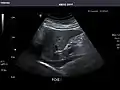

Right kidney

Kidneys: Right and left kidneys measure 11.5 cm and 12 cm in length respectively. No hydronephrosis. Small left lower pole kidney cyst.